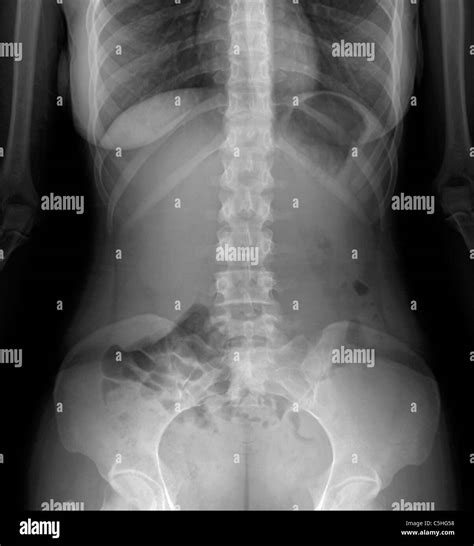

A Belly X Ray, also known as an abdominal X-ray, is a type of radiography that uses low doses of ionizing radiation to produce images of the internal structures of the abdomen. These images help healthcare professionals identify abnormalities, such as blockages, fractures, or foreign objects, that may not be visible through physical examination alone.

Interpreting the results of a Belly X Ray requires specialized training and expertise. Radiologists analyze the images to identify any abnormalities or signs of disease. Common findings include:

Radiologists may also use the images to assess the size and shape of organs, such as the liver, spleen, and kidneys, to detect any abnormalities.